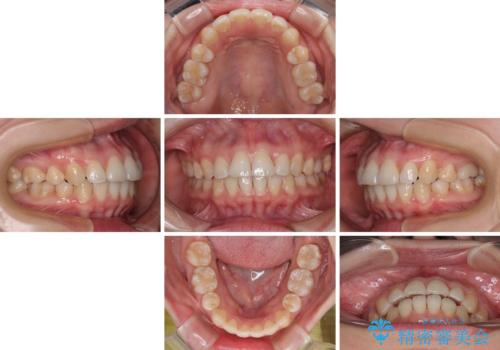

- 上下前歯の後戻りを気にして来院された患者様です。

インビザラインでの治療を希望されていて、デコボコの程度が中等度であり、安価なパッケージにて対応可能と判断されたため、インビザライン・モデレートを用いて矯正治療を行うこととしました。

インビザライン・モデレートは、製作できるアライナーの枚数に制限があるため、移動可能な量に限りがあるものの、インビザライン・ライトよりも枚数が多いため、幅広い症例に対応可能です。